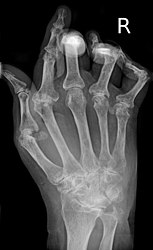

X-ray of the wrist of a woman with rheumatoid arthritis, showing unaffected carpal bones in the left image, and ankylosing fusion of the carpal bones 8 years later in the right image.

The disease progresses by forming granulation tissue at the edges of the synovial lining, pannus with extensive angiogenesis and enzymes causing tissue damage.[52] The fibroblast-like synoviocytes have a prominent role in these pathogenic processes.[19] The synovium thickens, cartilage and underlying bone disintegrate, and the joint deteriorates, with raised calprotectin levels serving as a biomarker of these events.[53]

X-rays of the hands and feet are generally performed when many joints affected. In RA, there may be no changes in the early stages of the disease or the x-ray may show osteopenia near the joint, soft tissue swelling, and a smaller than normal joint space. As the disease advances, there may be bony erosions and subluxation. Other medical imaging techniques such as magnetic resonance imaging (MRI) and ultrasound are also used in RA.[22][55]